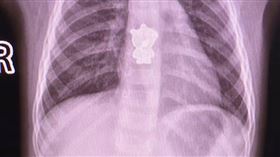

1歲童咳嗽咳出血 拍CT驚見佩佩豬

小孩子喜歡把物品塞嘴巴裡,家長務必要隨時緊盯,以免吞...

2020/12/27 14:48